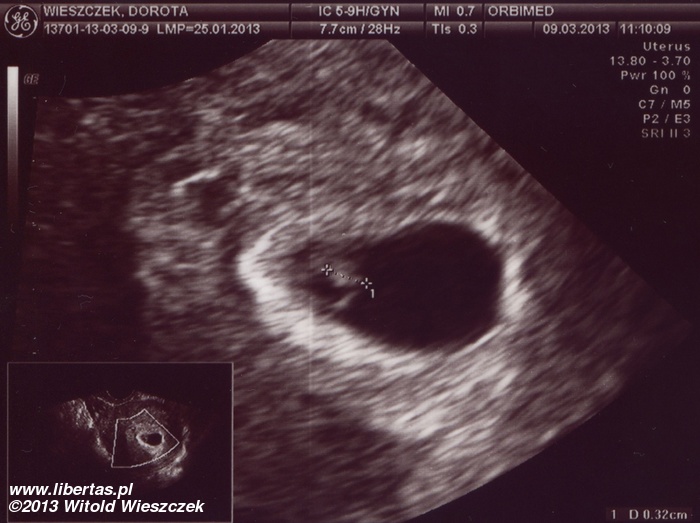

Księżniczka Dobrawa Wieszczek urodziła się 20 września 2013 roku o godzinie 8:50 w Szpitalu Wojewódzkim w Tychach. Chyba nie mogła się doczekać, bo swoje przyjście na świat przyspieszyła o ponad miesiąc, ważyła więc tylko 2140 gram i rozciągała się na długość 46 cm. Ale w skali Apgar dostała pełne 10 punktów i choć z tymi wszystkim rurkami wyglądała kosmicznie, to była zdrowa i czuła się świetnie.